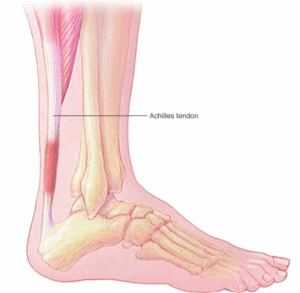

Achilles tendinitis

Achilles tendon rupture

Achilles (uh-KILL-eez) tendon rupture is an injury that affects the back of your lower leg. It mainly occurs in people playing recreational sports.